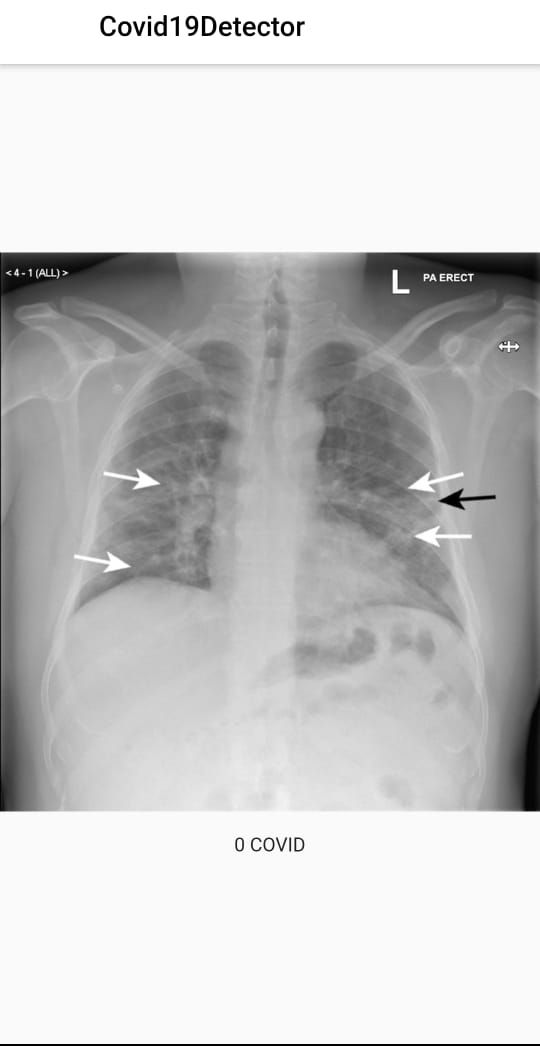

1-Covid detection through lung x-ray using a Kaggle dataset and embedding in the flutter app through Tensorflow.